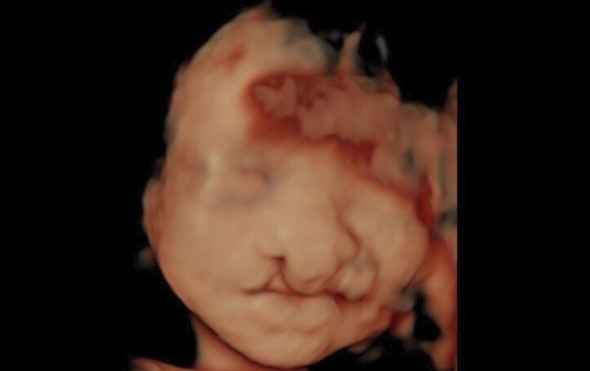

“一种疾病,一对母女,35年后遇到同一个医师,真的很令人动容。”某医生22日帮一名孕妇做高层次超声波检测,发现6个月的女宝宝有双侧唇颚裂,但家属却毅然决定生下宝宝。该名孕妇更透露,自己也是唇颚裂患者,曾在长庚整形外科接受手术修补手术,未来也会带着女儿找同位医师接受治疗。

要确认胎儿是否有唇颚裂,可在怀孕20周左右透过超声波检查得知。若发现罹病,会建议孕妇做羊膜穿刺与羊水晶片检查染色体,“以路段做比喻,羊膜穿刺大概只能看到大条的马路,但羊水晶片则可以看到几巷、几弄,增加精准性”,若只是单纯的唇颚裂,通常会建议家属保留胚胎。